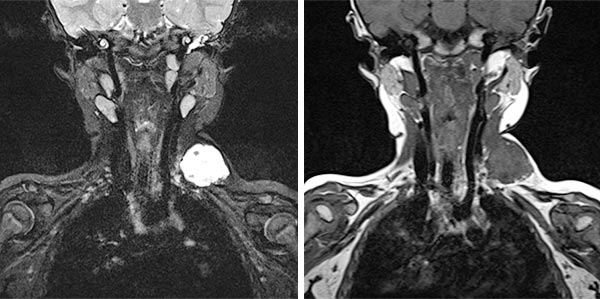

In der koronaren MRT (linkes Bild: T2-Wichtung, rechtes Bild: T1-Wichtung nativ) ist die venöse Malformation sehr gut abgrenzbar. In der T2-Wichtung ist sie stark hyperintens, in der nativen T1-Wichtung isointens zur Muskulatur. Die Signalgebung ist klassisch für den Charakter einer Slow-flow-Läsion.

In der koronaren MRT (linkes Bild: T2-Wichtung, rechtes Bild: T1-Wichtung nativ) etwas weiter dorsal, ist sehr gut ein größerer Thrombus innerhalb der venösen Malformation abgrenzbar. In der T2-Wichtung ist dieser hypointens im Vergleich zur stark hyperintensen VM. In der nativen T1-Wichtung ist er ganz gering hyperintenser als die umgebende hypointense VM.